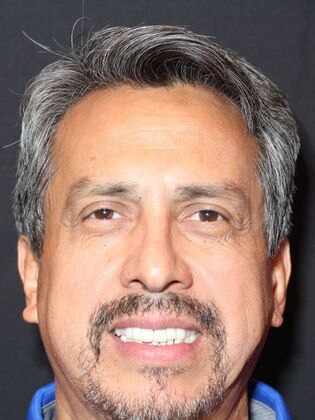

Dental Implants: Oscar

Description

Patient had posterior teeth that were old root canal treated teeth with porcelain fused to metal crowns. Due to gum recession, the metal base of the crowns was exposed leaving a dark grey line around the margins. He had an overall smile makeover and many old teeth replaced with dental implants. The key to a successful smile makeover is not being able to tell which ones are dental implants.